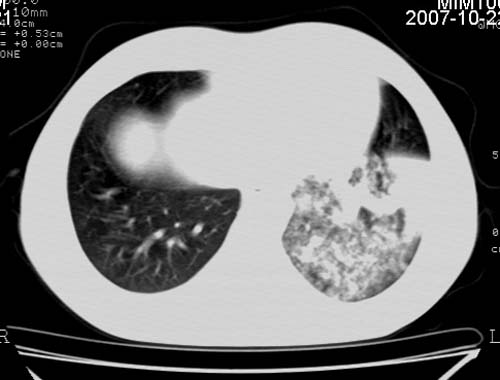

男,21岁,咳嗽、胸闷、乏力伴多汗二十余日、无明显发烧。患者一般情况好,为初三学生。

右肺上叶前段及左肺下叶多形性病变伴厚壁空洞,周边示树芽征.左肺下叶不张改变.

考虑;肺结核,不除外左肺下叶支气管内膜结核.

双肺继发性肺结核伴左侧空洞形成!不除外合并霉菌感染!(双肺多发病灶,左侧病灶形成空洞,并空洞内见壁结节。建议改变体位,观察空洞内结节情况,以便排除霉菌感染!)

左下肺实变能给出合理解释吗?